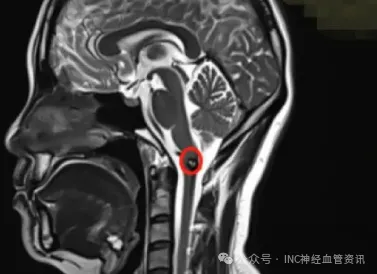

2017年,连续两周每日工作至深夜后,王女士出现典型临床症状。"当天下午突发单侧头部、面部及上肢麻木,呈现明显的电击样感觉,甚至影响持筷功能,伴有耳部闷胀感。"次日头颅MRI检查确诊为延髓海绵状血管瘤急性出血。

2019年复查影像显示病灶增大0.5厘米,提示再出血风险。尽管多数医生仍强调手术风险,也有部分专家建议手术治疗。